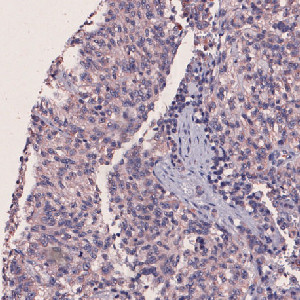

Nuclei surrounded by m-PGES1 negative and weakly positive staining.

The “10132 – m-PGES1, Melanoma, TME” APP detects nuclei and classifies them as either negative, 1+, 2+ or 3+ based on the m-PGES1 staining expression present in each nucleus’ vicinity.

To identify the nuclei, the APP performs a two-stage polynomial blob filtering on a blue-enhanced feature image and delimits them using local linear filtering. Each pixel with DAB staining is classified as low, mid and high based on the intensity and grouped together locally. Each nucleus is then classified based on its surroundings in the order of 3+, 2+, 1+ and negative to emphasize the strongest staining present in each nucleus’ vicinity.